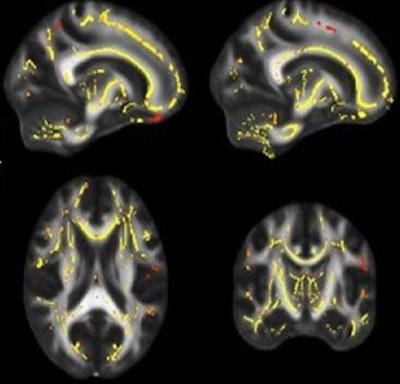

DTI-MRI highlights areas (yellow and reddish pixels) where the functionality of white matter is associated with higher fitness levels. The images are based on cumulative data from patients to show potential links between physical fitness and deterioration of white matter. Images courtesy of UT Southwestern Medical Center.All participants underwent a battery of tests, including DTI to assess white-matter fiber integrity, a method known as maximal oxygen uptake to measure the subjects' cardiorespiratory fitness, and memory and other cognitive tests to measure brain function. By doing so, the researchers aimed to determine correlations between exercise, brain health, and cognition.